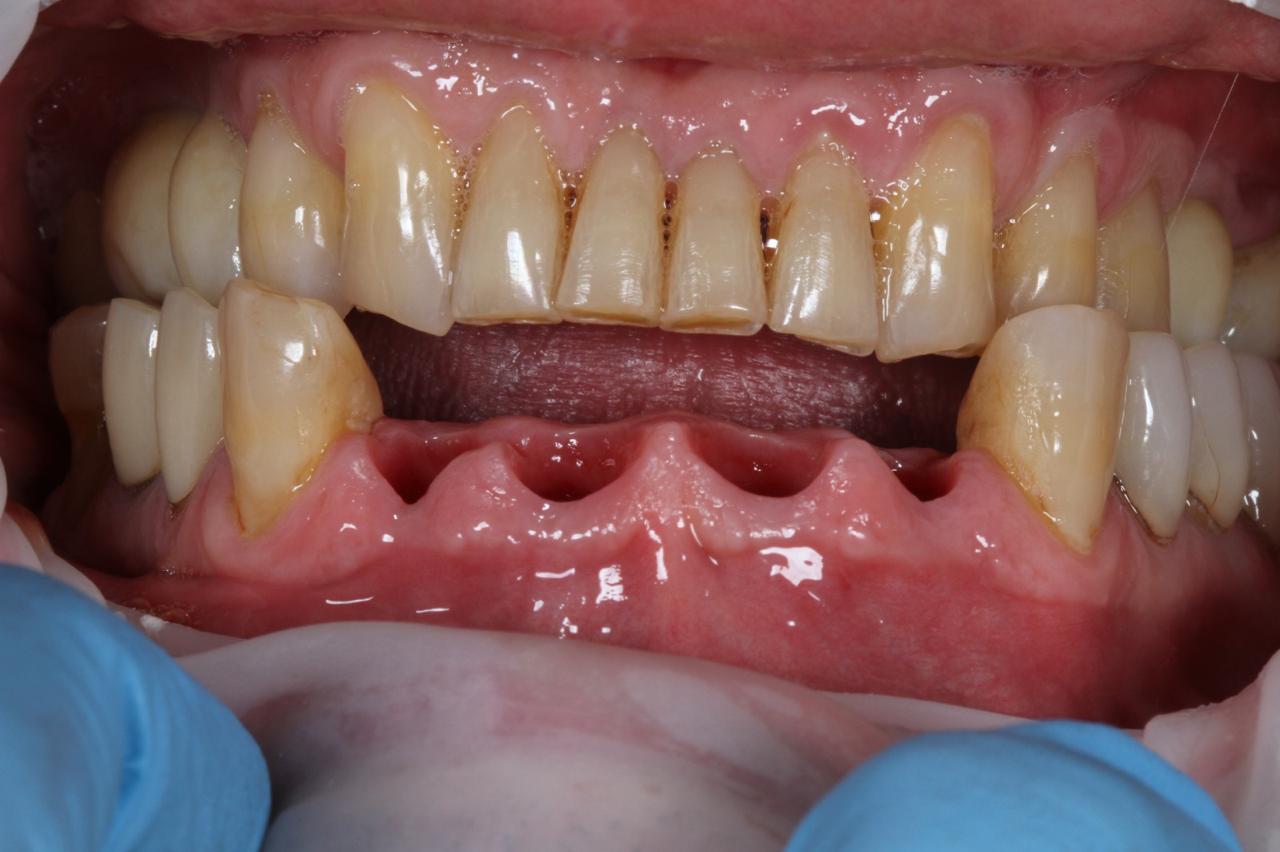

- Комплексное лечение стоматологических больных, в том числе с привлечением смежных специалистов. Функциональный анализ. Компьютерное моделирование и планированание.

- Планирование и функциональна реабилитация пациентов с полным отсутствием зубов с применением дентальных имплантатов.

- Парадонтологические операции (открытый кюретаж, лоскутные операции).

- Лечение периимплантитов